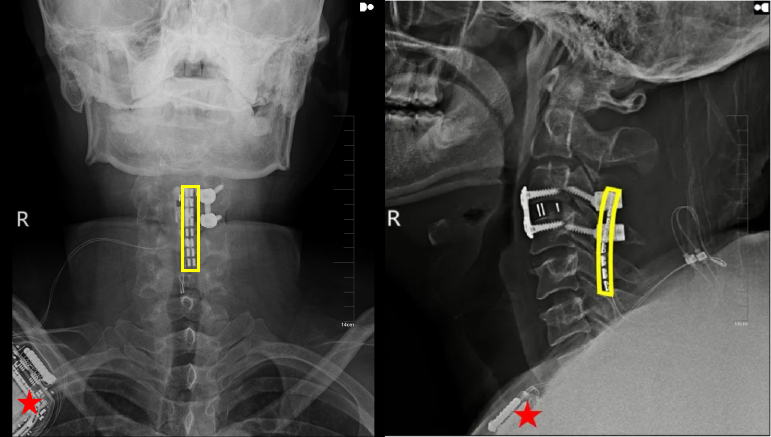

上图:植入术后X线显示,黄色方框为电极位置,星号为皮下脉冲发射器位置